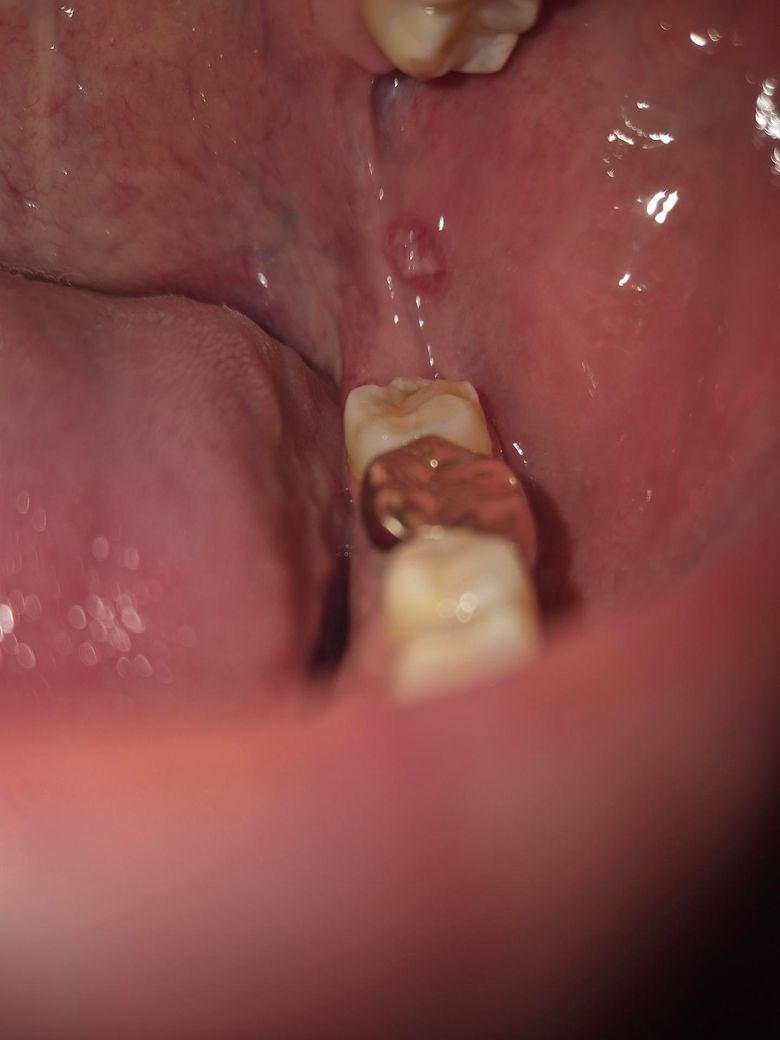

2개월째 구강 내 염증이 안없어지는데 뭘까요?

첨부삼 사진처럼 염증이 2개월째 안 없어지고 작아졌다 커졌다 반복하는거같은데 뭘까요?

병원을 가야한다면 치과나 이비인후과중 어떤 병원으로 가야할까요?

• 1번 째 사진